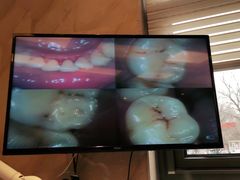

• 劲松口腔医院(蓝色港湾院)

• -劲松口腔医院(蓝色港湾院)

兰酱Julie | 21-12-12